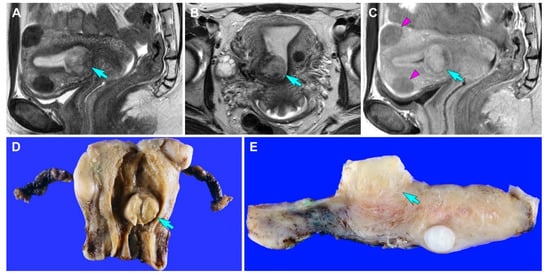

3.2.1. Clinical Presentation

3.2.2. Pathological Findings